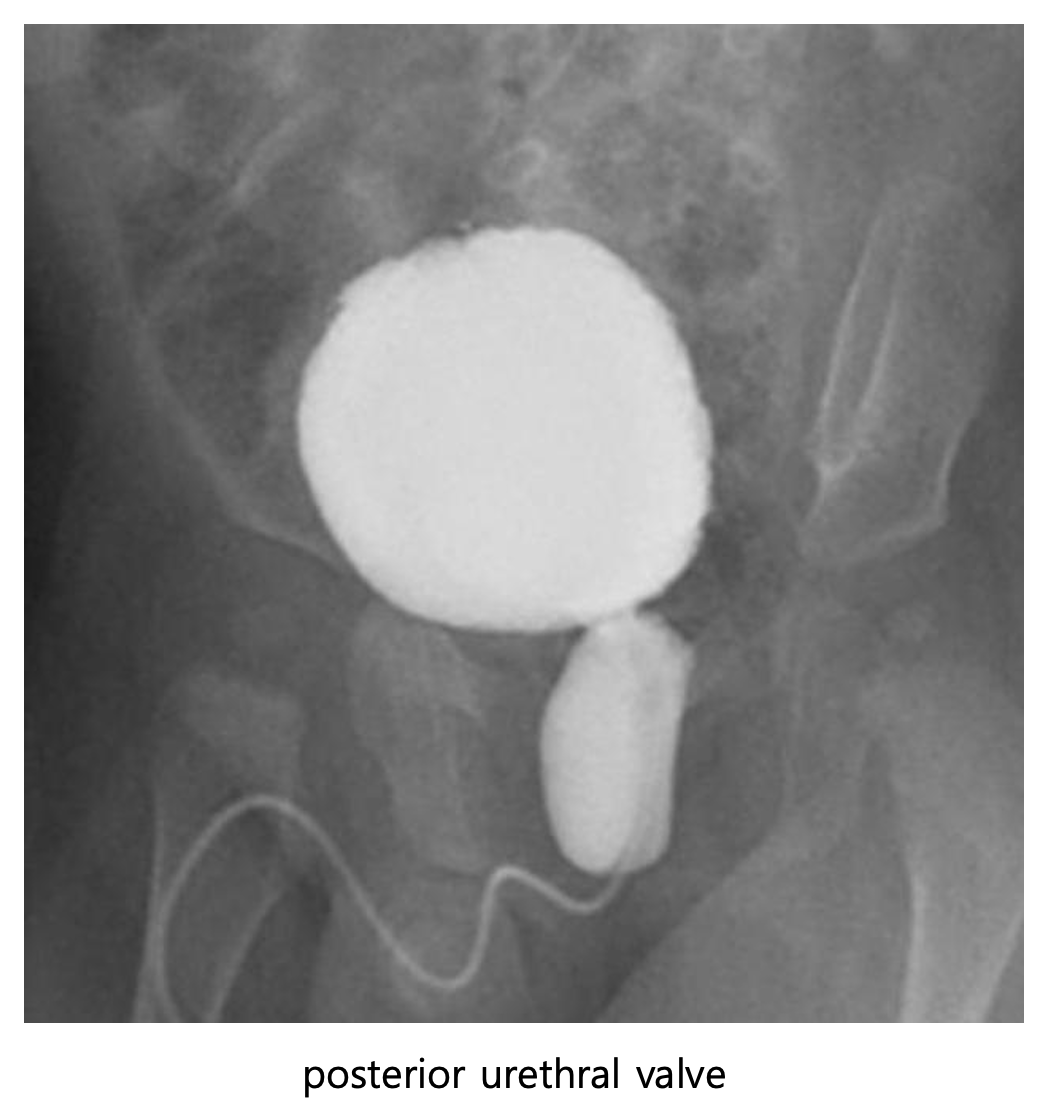

• posterior urethral valve